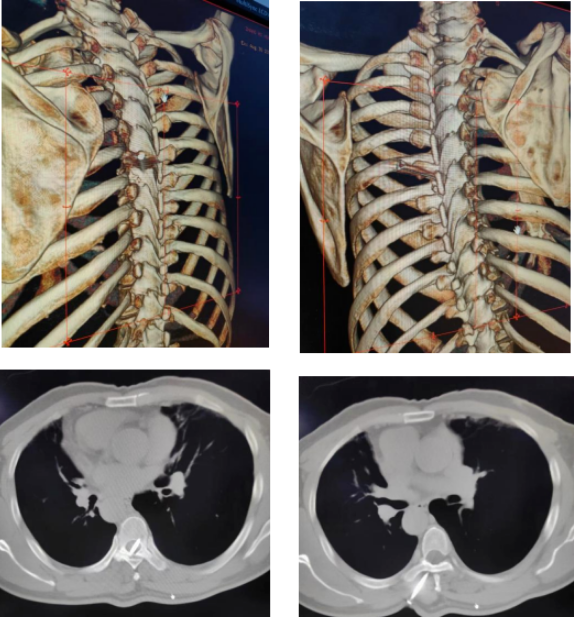

到達(dá)醫(yī)院后,急診科醫(yī)生針對張先生的情況迅速完善相關(guān)專科檢查,急請骨科醫(yī)學(xué)部張尊副主任醫(yī)師及冉博主任醫(yī)師會(huì)診,兩位醫(yī)生不到五分鐘即趕赴現(xiàn)場判斷傷情。當(dāng)時(shí)張先生后背部只見鐵釘釘帽殘留于皮外,其余部分全部刺入身體,內(nèi)部情況不明。隨即為張先生進(jìn)行胸部三維CT檢查,顯示:10公分的鐵釘自左背部刺入背部肌肉,從胸7椎板斜向內(nèi)貫通,最后止于胸8椎體,整個(gè)鐵釘牢固的插在張先生的椎管內(nèi)。